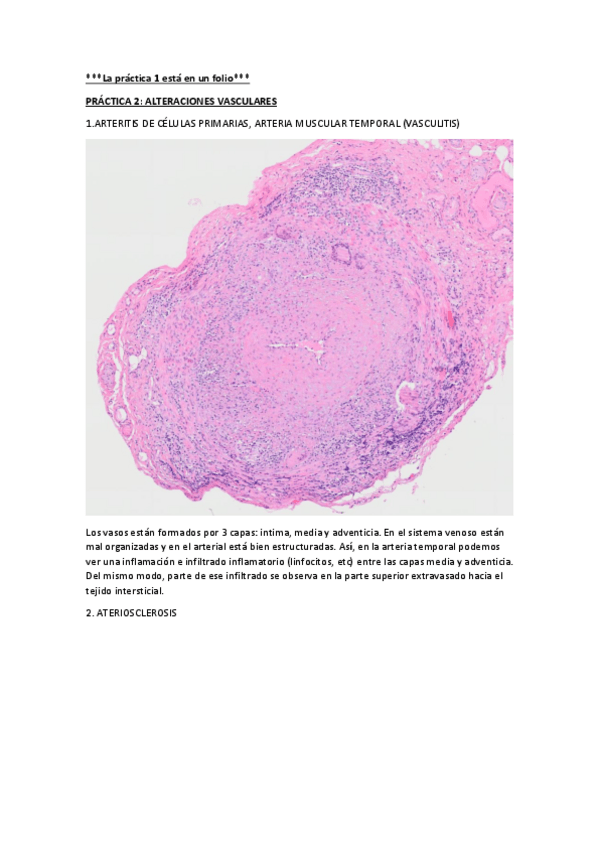

He publicado nuevos practicas de 2º Anatomía Patológica: PRÁCTICAS

PRACTICA-2.pdf